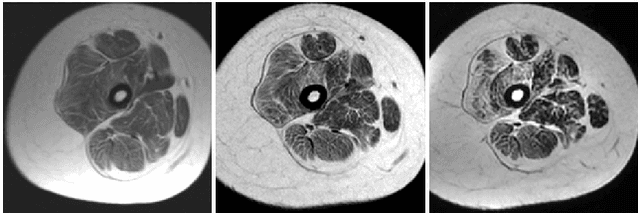

Abstract:Segmentation of skeletal muscles in Magnetic Resonance Images (MRI) is essential for the study of muscle physiology and diagnosis of muscular pathologies. However, manual segmentation of large MRI volumes is a time-consuming task. The state-of-the-art on algorithms for muscle segmentation in MRI is still not very extensive and is somewhat database-dependent. In this paper, an automated segmentation method based on AdaBoost classification of local texture features is presented. The texture descriptor consists of the Histogram of Oriented Gradients (HOG), Wavelet-based features, and a set of statistical measures computed from both the original and the Laplacian of Gaussian filtering of the grayscale MRI. The classifier performance suggests that texture analysis may be a helpful tool for designing a generalized and automated MRI muscle segmentation framework. Furthermore, an atlas-based approach to individual muscle segmentation is also described in this paper. The atlas is obtained by overlaying the muscle segmentation ground truth, provided by a radiologist, after image alignment using an appropriate affine transformation. Then, it is used to define the muscle labels upon the AdaBoost binary segmentation. The developed atlas method provides reasonable results when an accurate muscle tissue segmentation was obtained.